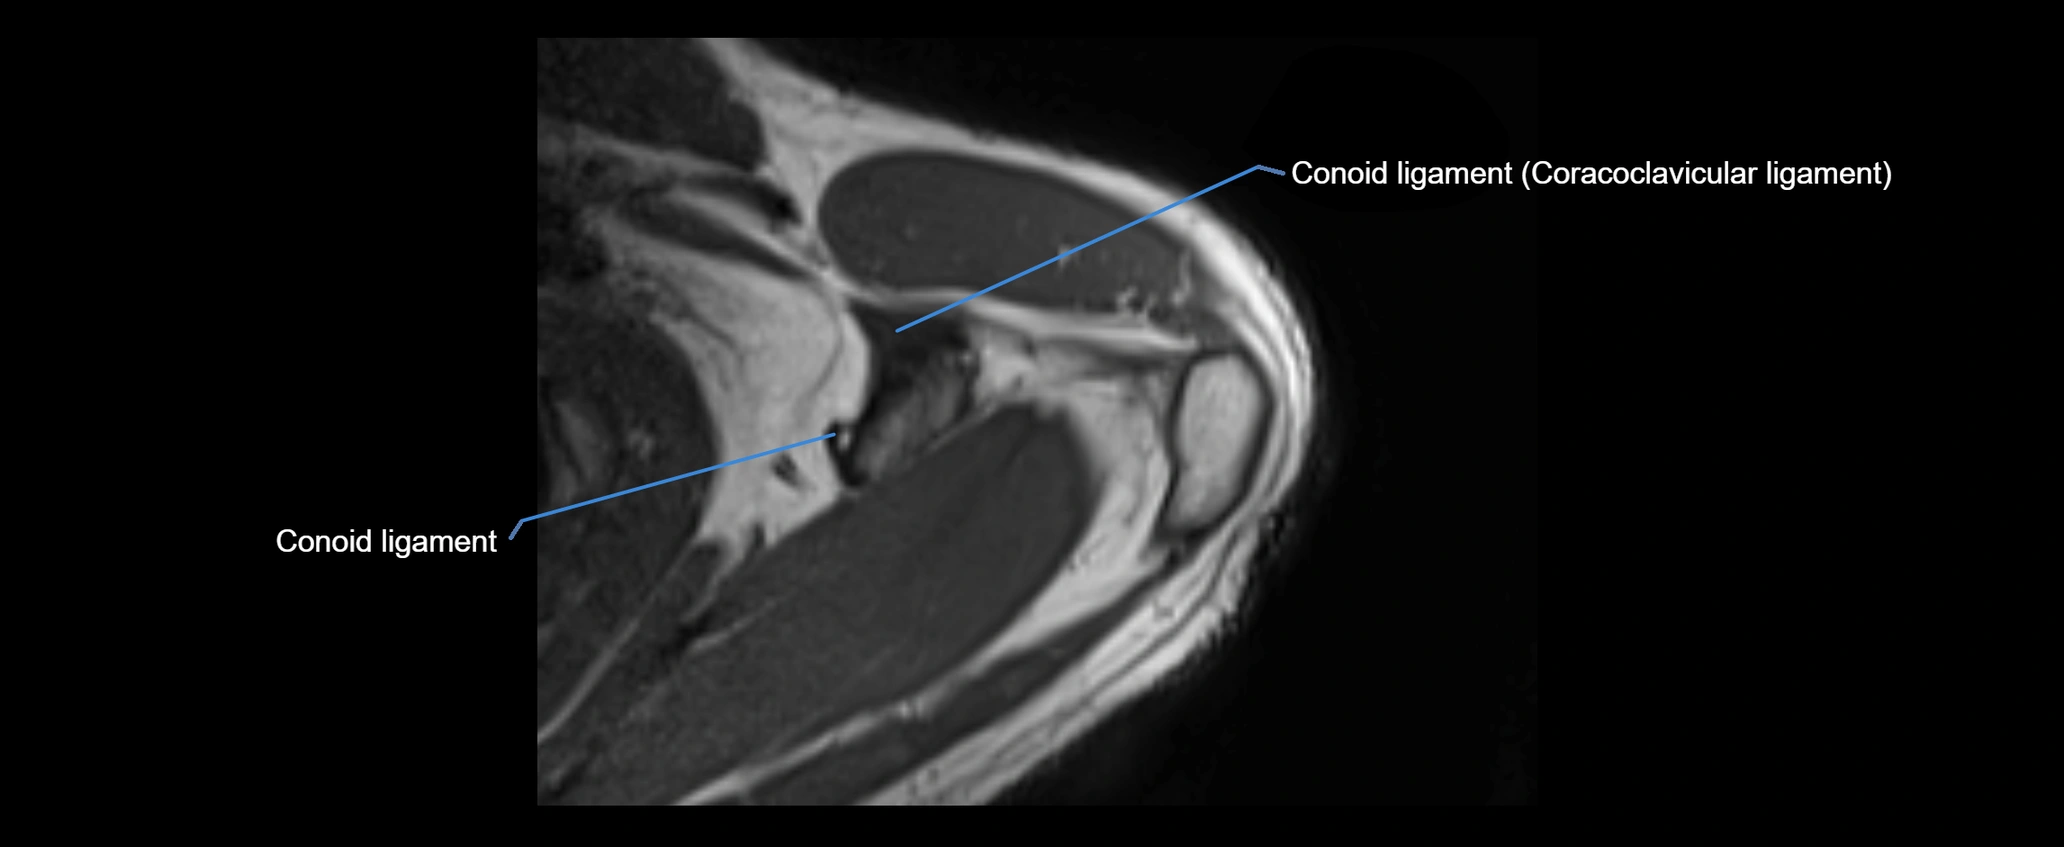

MRI images

image

• Proton Density Fat-Saturated (PD FS):

• Normal ligament: Low signal, uniform thickness.

• Partial tear or sprain: Bright signal or contour irregularity.

• Complete tear: Clear discontinuity with bright signal gap and joint effusion.

• Excellent for assessing joint capsule, coracoclavicular ligaments, and periarticular edema.